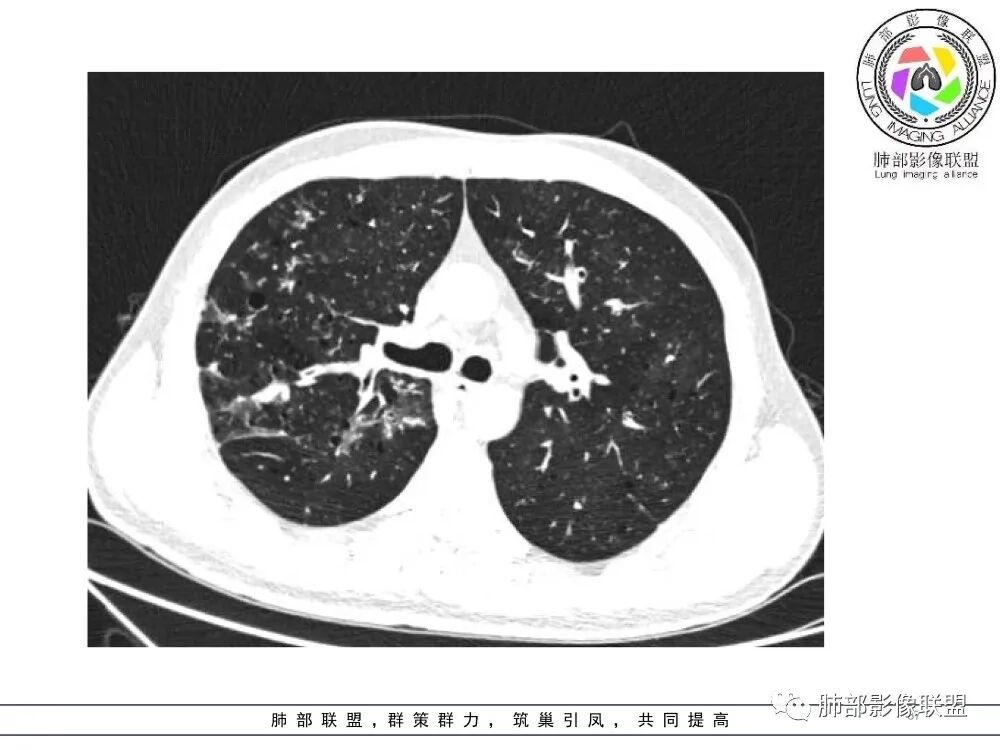

中年男性,慢性咳嗽,有吸烟史,胸部CT基础尚可,双肺多发的沿支气管播散的树芽影以及支气管管壁的增厚和对应区域内的斑片影实变影,符合气道播散的表现。经过对症抗感染治疗1月之后,胸部CT影像进展。右侧播散到左侧。实变和漱牙以及气管壁增厚均较前明显进展。

两肺多发弥漫性腺泡结节,支气管壁增厚,抗炎治疗后病变范围较前进展,沿支气管血管束分布,两肺见多发树芽及增厚扩张支气管,以右中叶及左上叶舌段为著,年轻患者,慢性病史,扩张支气管周围肺野未见肉芽肿性病变,抗炎治疗无效可排除诺卡及铜绿感染,综合分析首选NTM,其次气道侵袭性曲霉。

两肺支气管壁增厚,散在斑片状及树芽状影,抗炎治疗后病变范围进展,沿支气管血管束分布,两肺多发结节、树芽、实变及囊腔影,年轻患者,慢性病史,肺气肿背景,考虑气道侵袭性曲霉,鉴别NTM+铜绿。

两肺广泛支气管轻度扩张及管壁增厚,厚薄稍不均,累及叶段支气管,周围见散在斑片状密度增高性,部分实变,边缘模糊,下叶为著。考虑炎症,首先气道侵袭性曲霉,ntm待排。

晨读:最关键的有三点:1、临床表现及病史:35岁,男性,慢性刺激性咳嗽2月,吸烟史17年,没有糖尿病和其他免疫缺陷病史。这儿应该隐瞒了关键的吸入环节,存在大量曲霉孢子的工作环境没给。2、第一次影像改变:广泛的支扩,支气管壁增厚,多发的树芽,部分区域已经伴有支气管周围的渗出,少量实变。3、20多天后复查的影像,原有支扩,支气管壁增厚基础上的大量渗出,实变,伴结节,胸膜下累及。

上述表现最符合的就是气道侵袭性曲霉菌病(IPA),刺激性咳嗽2月支持最初的气道改变:广泛的支扩,支气管壁增厚(支气管粘膜充血,水肿,以及伪膜形成)树芽征,而后期大量支气管周围渗出,实变,伴结节,胸膜下累及,也符合IPA的进展表现,病史中未提及是否有胸闷,气喘等(估计后期有,没提供而已)。

35岁男性,慢性咳嗽2月余,吸烟17年。弥漫支气管壁增厚,腔部分增宽,部分狭窄,远端粘液栓,树芽征,边界模糊,抗炎无效。

6/13复查,外围出现斑片状实变影,周围GGO,从发病过程:支气管壁增厚,延续到小气道炎症,然后周围实变,首先气道来源病变,因为支气管壁的增厚,腔狭窄、扩张,其次病变广泛,几乎累及所有叶段,常规思路:气道侵袭性曲霉菌病;不除外努卡。与NTM鉴别,NTM其实支气管扩张为中型的多为中外带支气管扩张,中近端支气管改变不明显,这个中内带明显,而且早期是中内带为主。

2.胸部CT:两肺广泛的支扩,支气管壁增厚,多发的树芽影,部分伴有支气管周围的渗出,少量实变。不足一月复查,原有支扩、支气管壁增厚基础上伴有大量渗出,实变,结节,胸膜下累及。

3.综合分析:首先病灶沿支气管分布,呈树芽征及实变影,相应支气管壁广泛增厚,其次病变范围比较广泛,几乎累及所有叶段,这种表现常高度提示气道播散,经过对症抗感染治疗20多天后,胸部CT影像明显进展。符合IPA的进展表现。